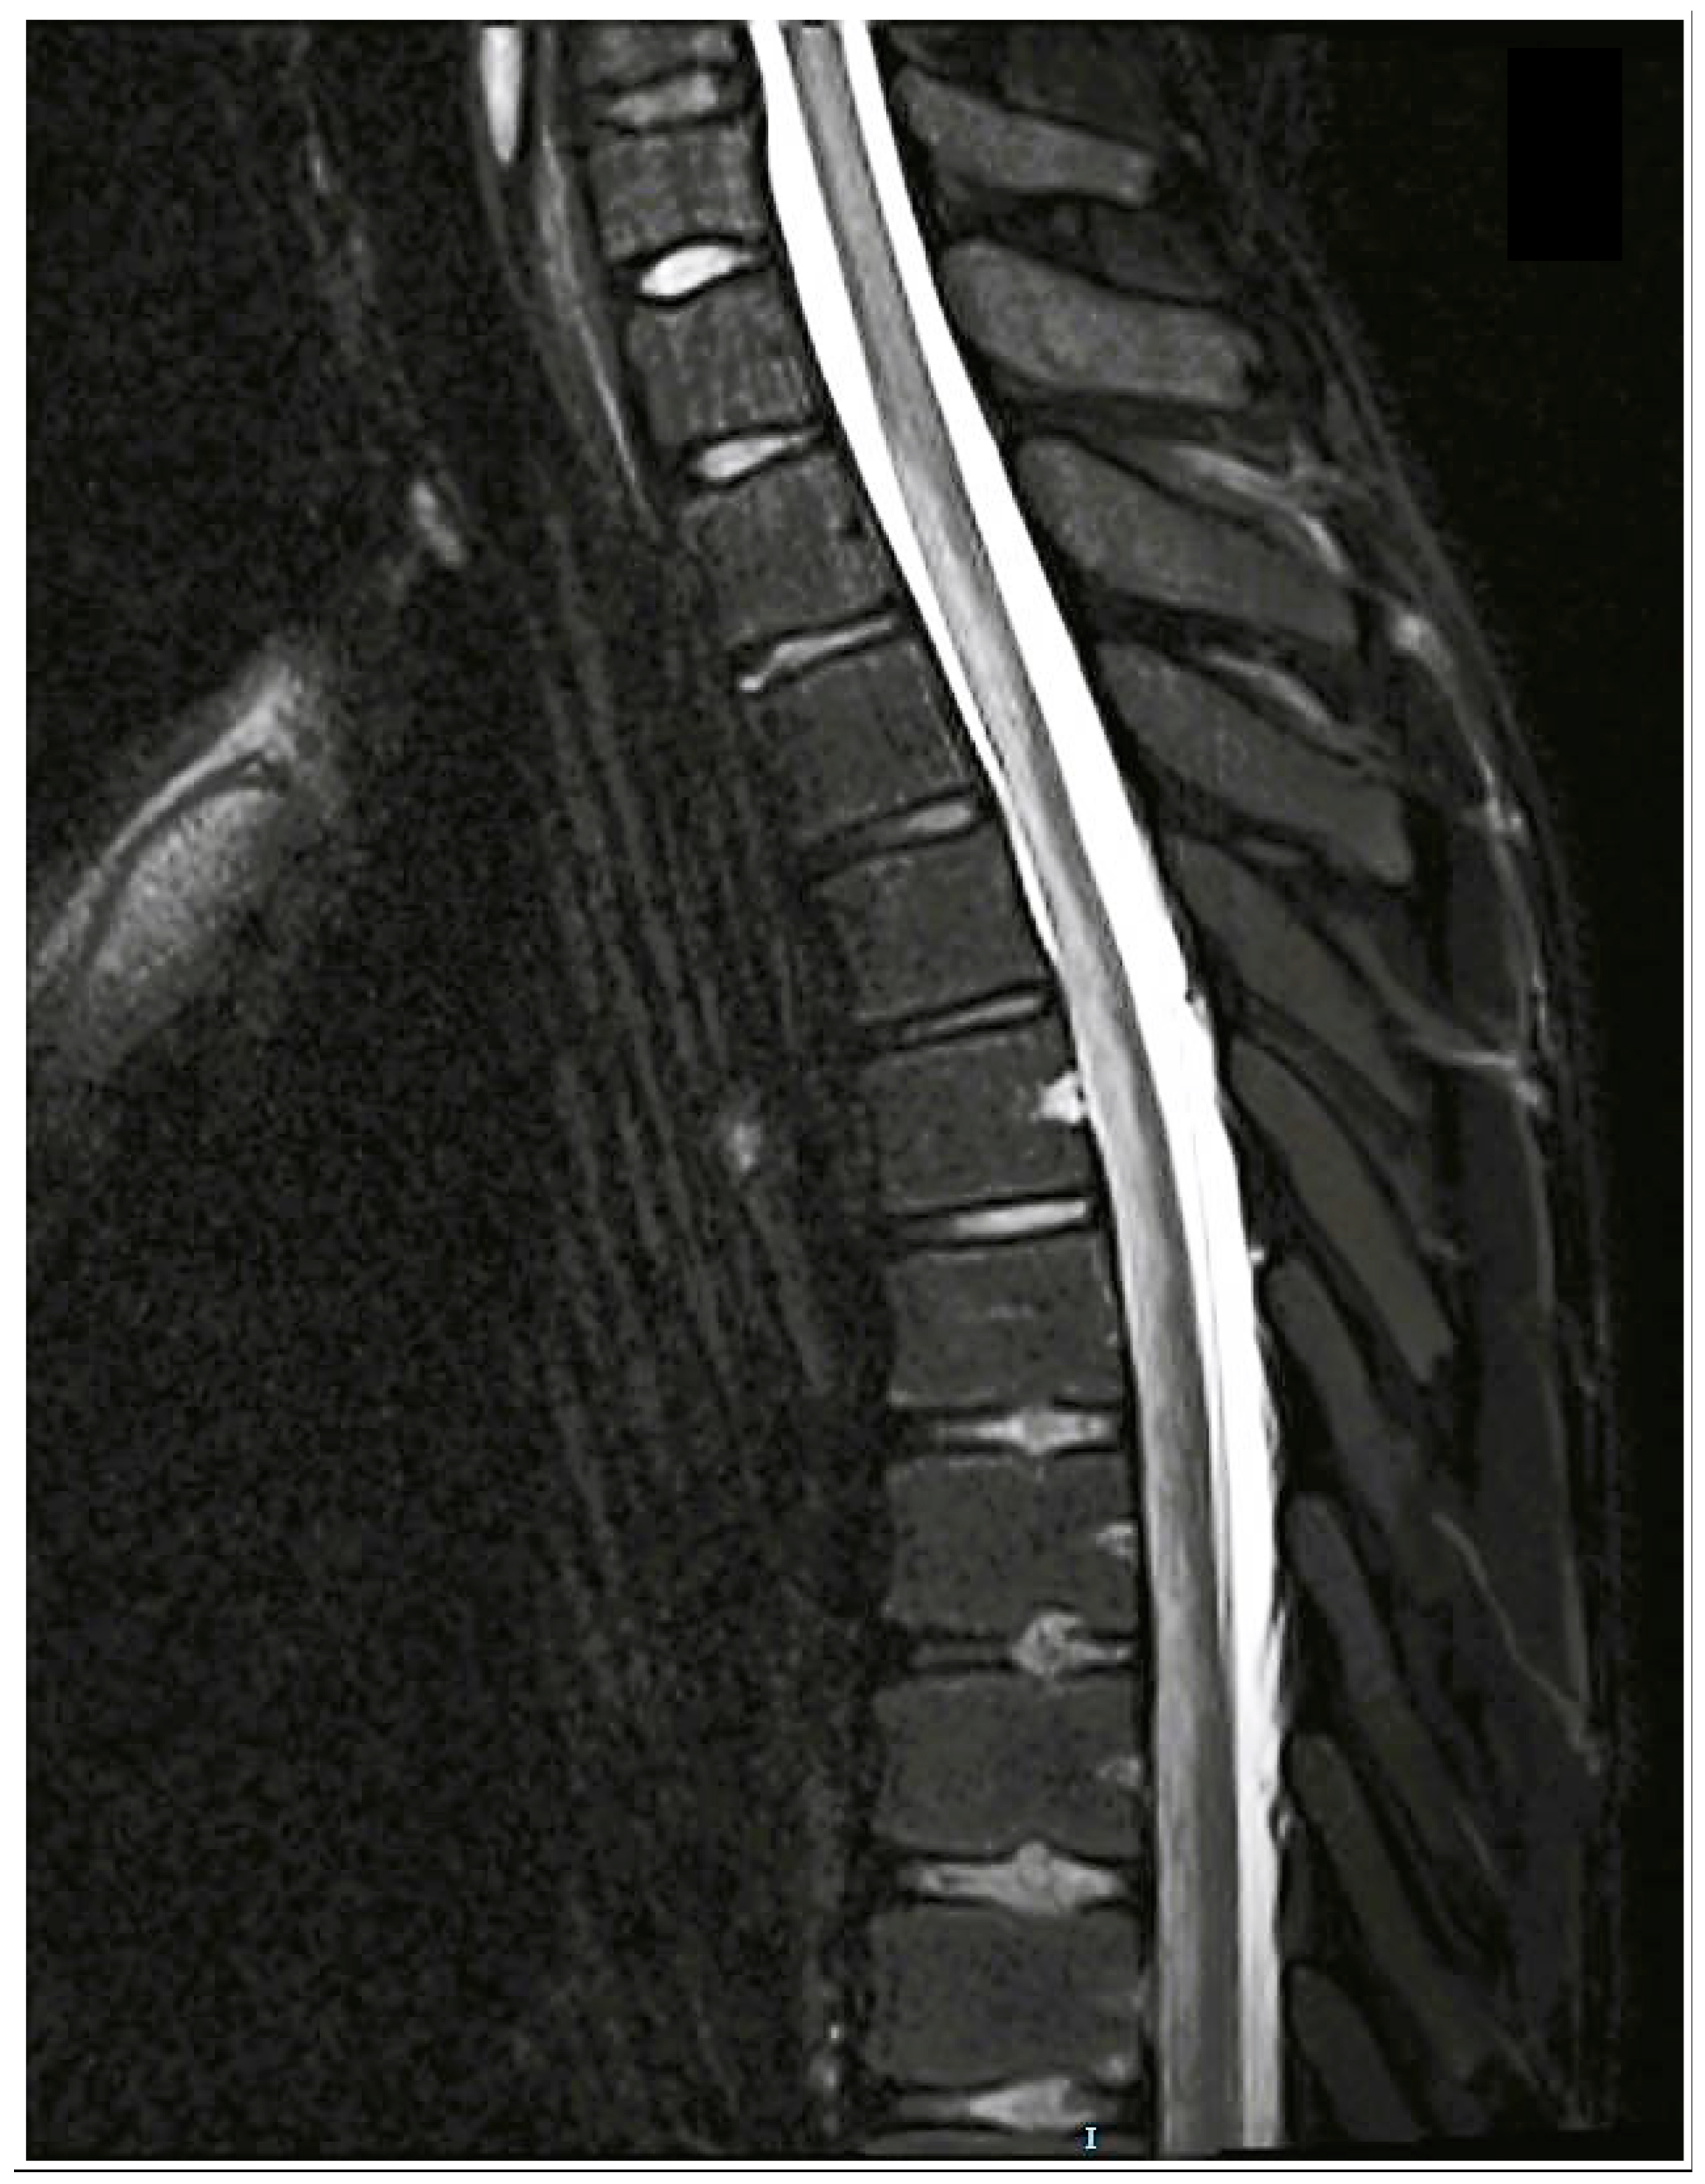

3.3.2. Imaging